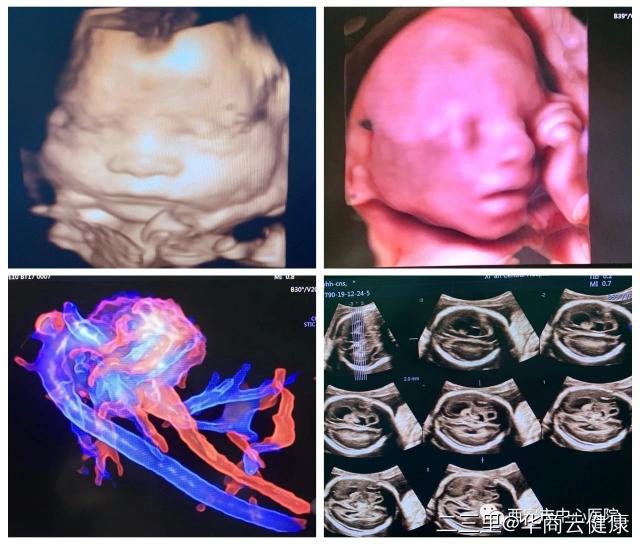

轻度的侧脑室增宽,其往往是一个排除性诊断,该征象可为一些隐匿性的脑发育异常的唯一超声表现,也可以是正常胎儿的颅内声像,同样图像的预后可能存在明显差异,侧脑室宽度持续性小于1.2CM者,通常预后较好,孩子大多正常,大于1.5cm者预后较差(但依然有一部分出生后正常)。发现这类软指标后,超声医生将为胎儿应用容积成像、线断层成像、VCI成像等多种模式进行全面评估,必要时组织科室会诊(所以产检选择仪器先进,技术过硬的团队很重要!)。西安市中心医院超声诊断科是陕西省产前超声筛查中心,配备最先进的Voluson E10、煊光Voluson E8等高端四维彩超,将为大家提供全方位高质量服务,在临床应用上覆盖了生殖医学、产前筛查、早孕期筛查、胎儿心脏、妇科肿瘤等方面,全方位呵护妇女健康。